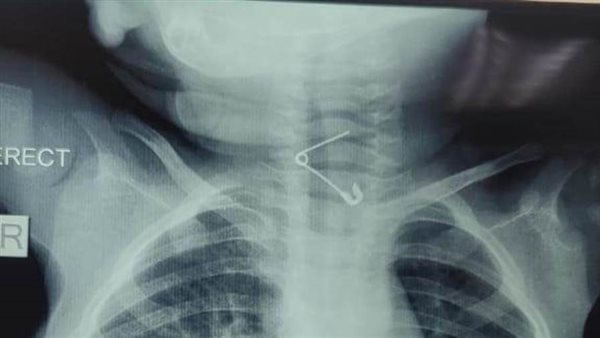

عمره عام.. إنقاذ حياة رضيع ابتلع "دبوس" بمستشفى الأطفال التخصصي ببنها

نجح فريق طبي بقسم جراحة الأطفال بمستشفى الأطفال التخصصى ببنها في محافظة القليوبية، في إنقاذ حياة طفل بلغ من العمر عامًا، ابتلع دبوسًا معدنيًا استقر في الحلق، مهددًا مسار التنفس ومسببًا خطورة بالغة على حياته.

العملية تطلّبت تنسيقًا فائقًا بين أطباء التخدير والجراحين، وتمّت بدقة متناهية لتفادي أي مضاعفات، في وقت قياسي، وسط متابعة مستمرة من الإدارة الطبية، واستعداد كامل للتدخل في حال حدوث أي طارئ.